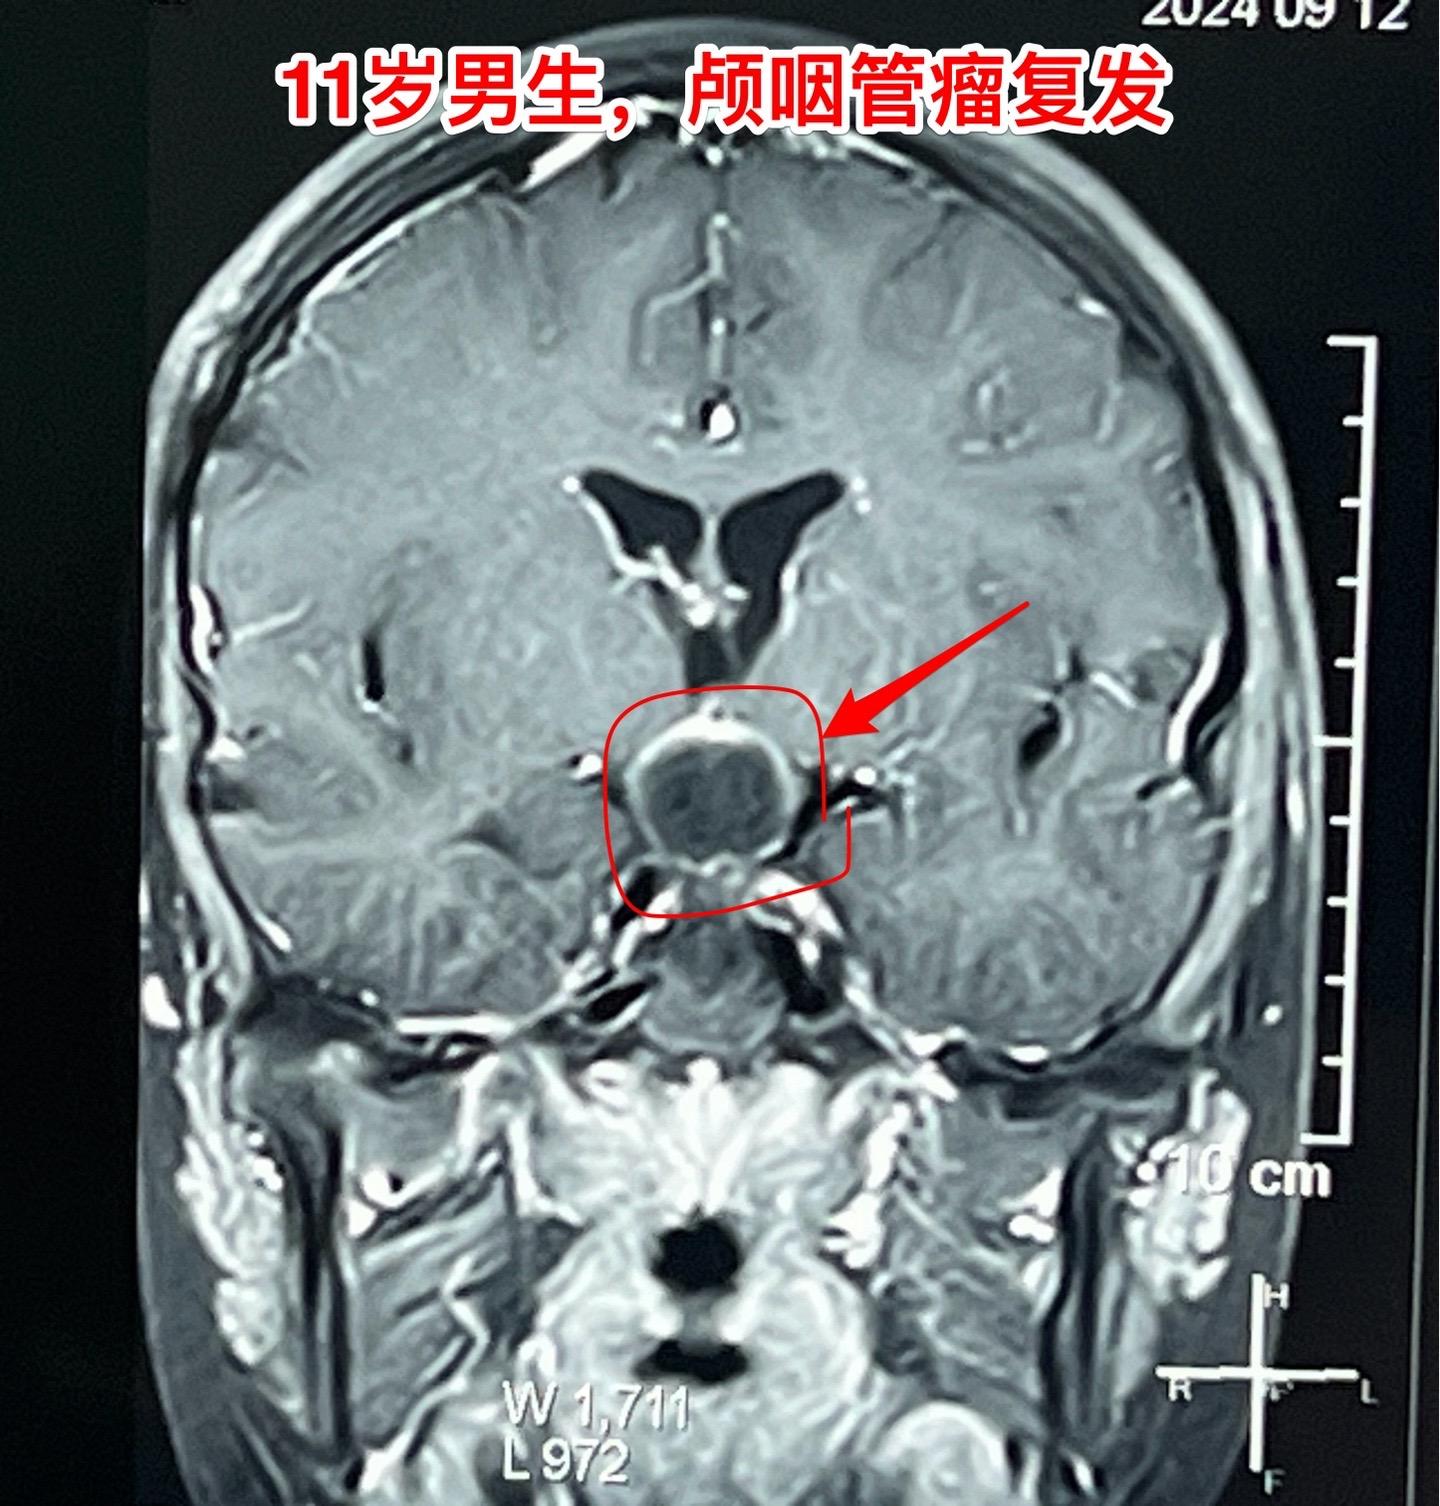

国庆节长假后第一天完成两个手术。一个手是33岁女性,来自云南省香格里拉。因左眼视力下降,到医院检查发现鞍区肿瘤,怀疑是颅咽管瘤。病人没有内分泌功能障碍。影像学上肿瘤是实性的,没有钙化,而且可以看见垂体信号。到底是什么肿瘤呢?今天手术中取肿瘤标本作快速冰冻病理检查,报告是垂体瘤。肿瘤得到完全切除,手术后病人视力好转了。 另一个手术是11岁男孩子,颅咽管瘤复发。经原切口翼点入路将肿瘤完全切除。术前磁共振只看见一个圆形肿瘤,术中发现除了这个肿瘤外还有5个散在的钙化斑,均得到完全切除。这样的散在钙化斑是潜在的危险因